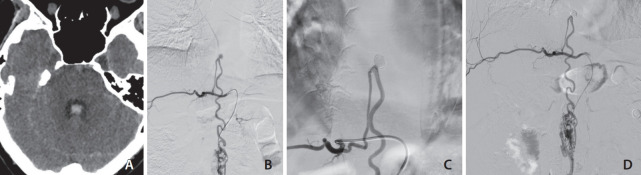

The present report describes a patient with spinal cord arteriovenous malformation (AVM) and an associated anterior spinal artery aneurysm presenting with subarachnoid hemorrhage. Diagnostic spinal angiography revealed an intramedullary AVM, located at the T10-T11 level, and a prenidal saccular aneurysm at the junction of the radiculomedullary artery and the anterior spinal axis, fed by the right T8 segmental artery. The patient underwent successful selective coil embolization of the aneurysm. Follow-up angiography 3 months postoperatively showed no recurrence of the aneurysm.